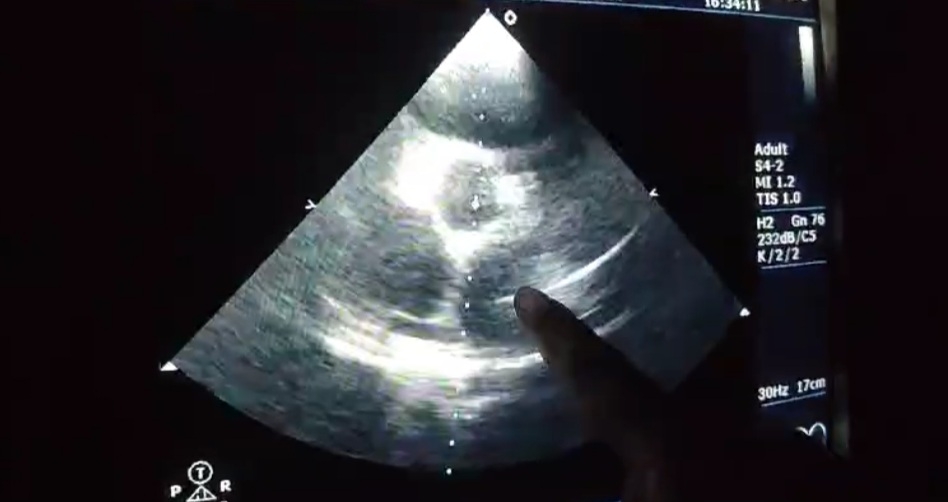

[27/10, 8:05 pm] Rakesh Biswas Sir: 👆How much is the RVSP written here?

[27/10, 8:11 pm] Navya Sri. Pabba: 75 mm Hg sir

[27/10, 8:14 pm] Rakesh Biswas Sir: And what is the severity of pulmonary hypertension written as?

[27/10, 8:39 pm] Navya Sri. Pabba: As No PAH  sir

[27/10, 8:39 pm] Rakesh Biswas Sir: How do we explain this discrepancy?

[27/10, 8:46 pm] Navya Sri. Pabba: Sir it is interpretation error

[16/10, 5:02 pm] Dr. Lohith Varma Jampana: 2decho!

[16/10, 5:02 pm] Navya Sri. Pabba: Review 2d echo

[16/10, 5:02 pm] Navya Sri. Pabba: Yes sir

[16/10, 5:13 pm] Dr. Lohith Varma Jampana: Dilated cardiac chambers have reversed sir!

INTERPRETATION OF 2D ECHO